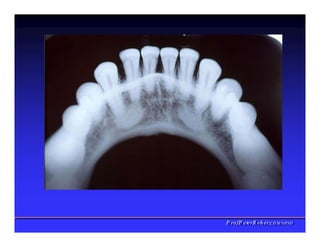

Parede Superior - Palato

Parede Superior -